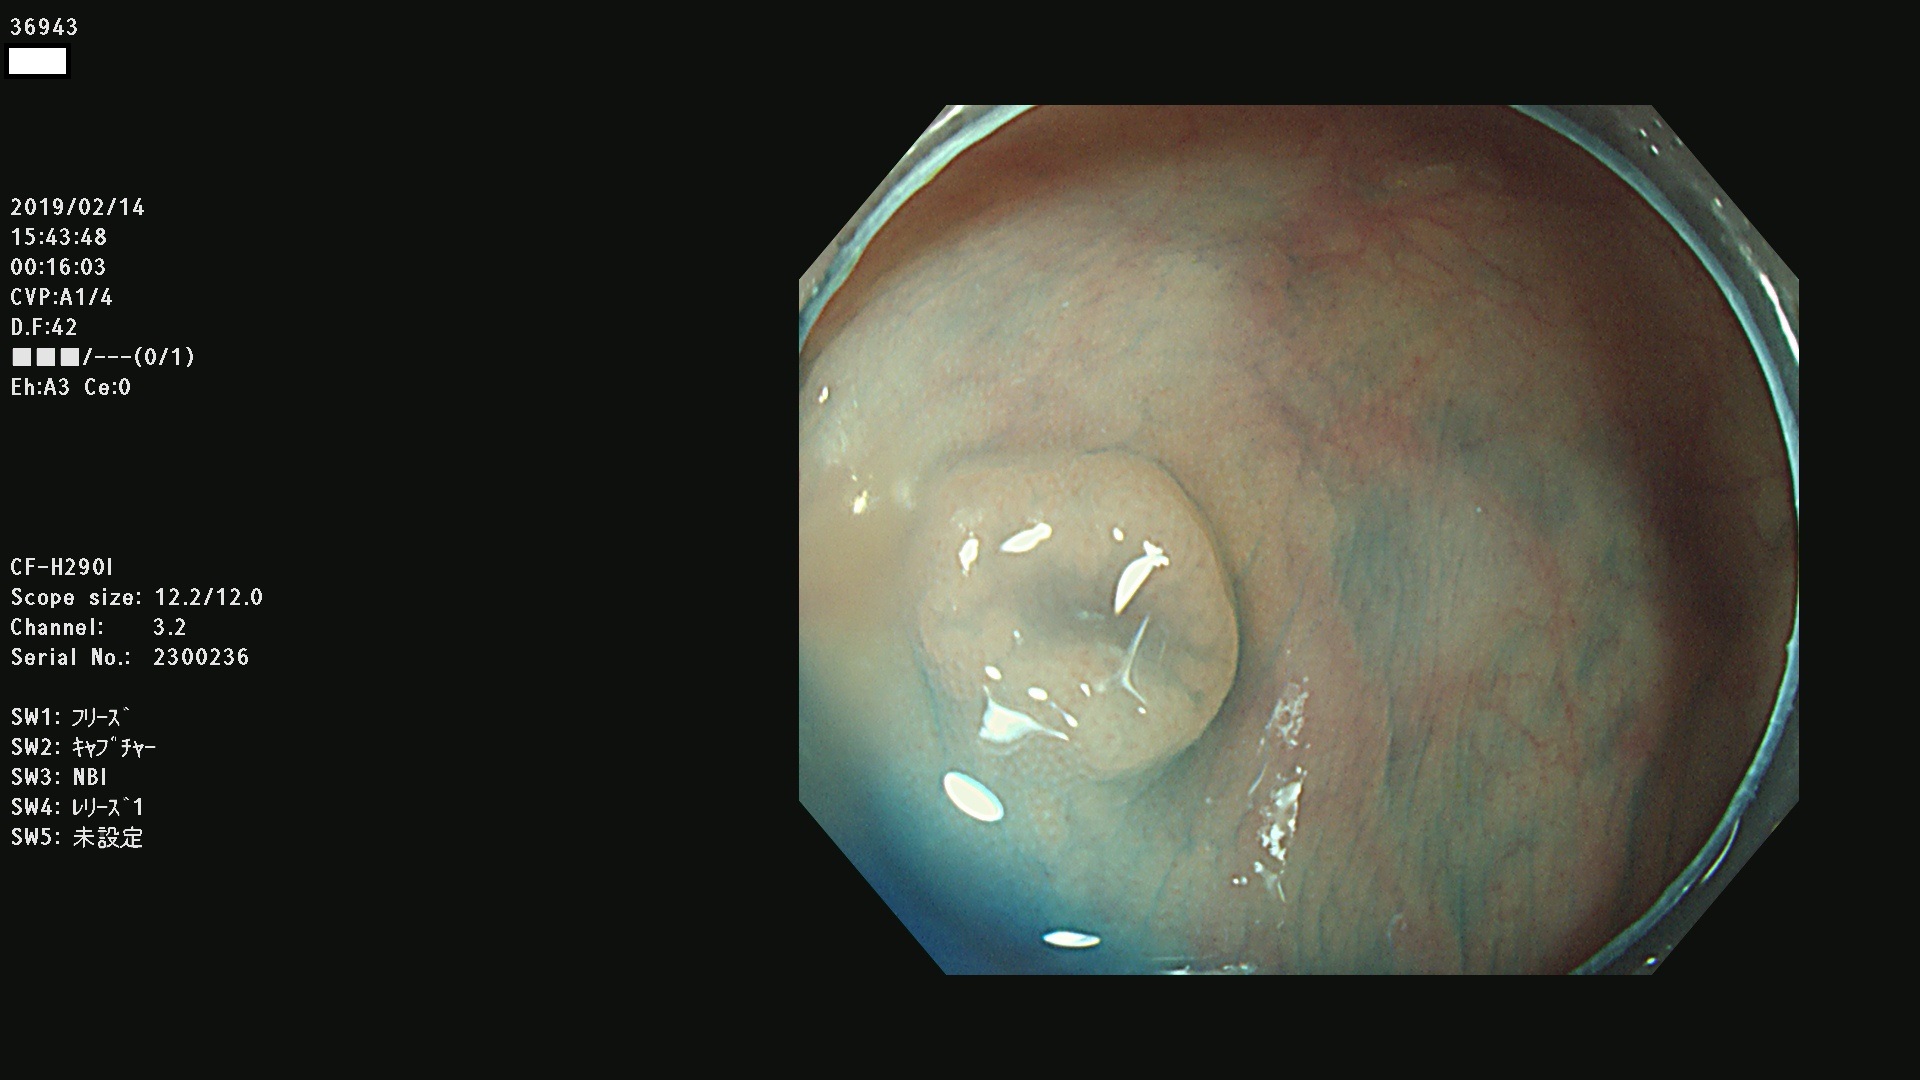

発見困難で危険性の高い平坦型病変(上記100名より抽出) ![]()